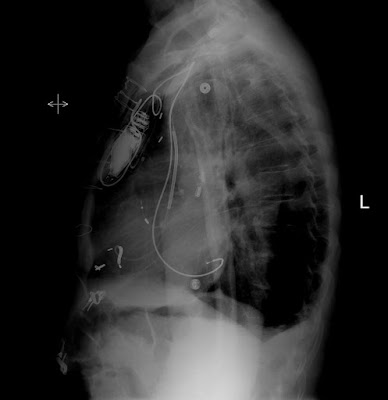

1. Looking at these films - Where are the 3 leads placed?

2. Ignore the pacemaker. What is the other catheter? Is it placed appropriately? Where is it recommended to be?

3. Ignore the pigtail drain and ekg leads. There is an abnormally placed tube. What is it? Where is it? What do you tell the care team to do after removing and/or repositioning (2 things)?

5. What type of catheter is this? Where is it supposed to be? Is it where it is supposed to be?